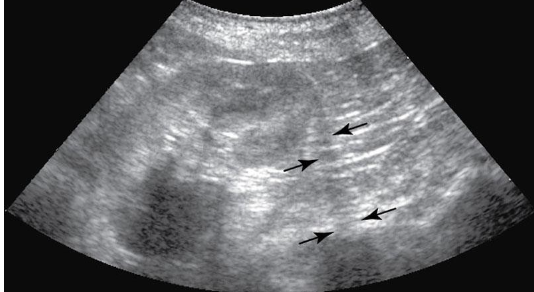

Reverberation (Ring Down)

highly reflective surfaces

sound waves bounce back and forth - produce echoic lines at regular intervals

commonly caused by gas or free air

Comet Tails

type of reverberation artifact seen with gas interfaces

smaller width strong lines produced

air pockets in GI tract or metallic objects, a foreign body, or tip of a biopsy needle